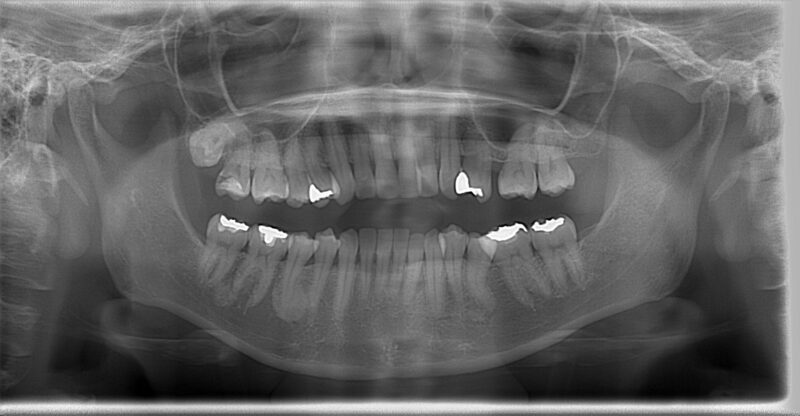

こちらが、初診時のAさんのレントゲンと写真です。

一見すると、大きな問題はないように見えるかもしれません。しかし、専門的な視点から分析すると、いくつかの重要な問題点が浮かび上がってきました。

最大の原因は、左上の前から2番目の歯(専門用語で「側切歯」)が、下の歯に強く引っかかり、顎がスムーズに動くのを妨げていたことです。毎日、食事や会話のたびに、この「引っかかり」が顎の関節や周りの筋肉に不自然な力を加え続けていました。これが、慢性的な頭痛や耳鳴りの引き金となっていたのです。

さらに、以前に左上の奥歯(5番目の歯)を抜いたままにしていたことで、歯並び全体が少しずつ変化し、かみ合わせのずれをさらに悪化させている状態でした。